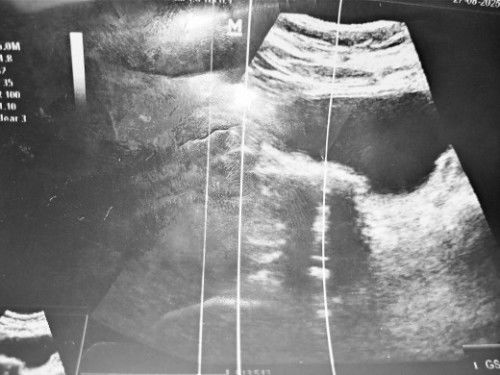

scan kehamilan 14 weeks blom dengar heartbeat,doc suh tunggu 2 week dtg scan smula tnye mne jnin@bby

kalau baby ikut week insyaallah takda apa ii mungkin alat mesin scan tu yg takbrp canggih sbb sy hritu pon sma , punya la menangis gelisah smua ad lps 2mggu check klinik lain ok je siap degup .jgn risau ye sis doa banyak ii ❤️.

pembesaran bb camne..ikut week x

ye...ikut week